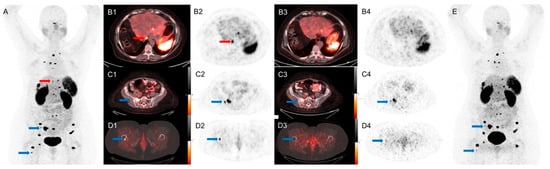

An example is shown in Figure 2.

Figure 2.

A 65-year-old woman with metastatic NET of unknown primary, referred for subsequent treatment strategy after chemotherapy. SiPM-based PET/CT was performed first at 72 min after injection of 4.2 mCi of 68Ga-DOTA-TATE. Conventional PET/CT was performed second at 96 min after injection. Red arrows mark an additional lesion seen in the dome of the liver only on SiPM-based PET/CT (A,B1), not on conventional PET/CT (B3,B4,E). Blue arrows mark bone lesions seen on conventional PET/CT (C3,C4,D3,D4,E) but more conspicuous on SiPM-based PET/CT (A,C1,C2,D1,D2).